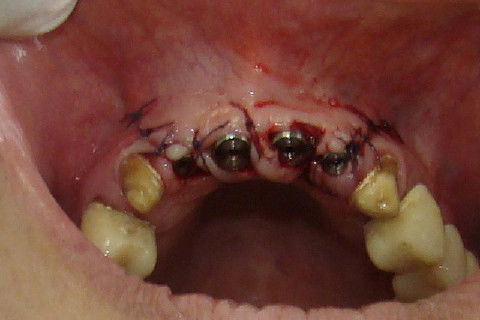

Preenchimento dos espaços existentes com osso particulado e proteção com membrana de colageno

Sutura da região anterior da maxila